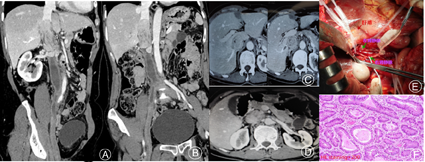

病例一:患者,女性,53岁,因双下肢反复浮肿2月余,腹痛1月余入院,既往体健,月经正常,已绝经,入院行CT静脉造影(CT venography, CTV)检查显示:肾静脉与肝静脉之间下腔静脉肿瘤,左肾静脉累及,考虑平滑肌肉瘤可能,并远端下腔静脉及右髂静脉血栓形成(见封四,图1Ⓐ,图1Ⓑ,图1Ⓒ,图1Ⓓ)。联合肝胆胰外科医师协助游离肝脏并暴露第一肝门肝动脉、门静脉及第二肝门处门静脉,阻断带预阻断,防止无法控制的出血。阻断第一、二肝门血流,于肝后段下腔静脉切开,见肿瘤与下腔静脉前管壁及左肾静脉粘连紧密,将肿瘤及粘连紧密的下腔静脉管壁及左肾静脉切除合,下腔静脉及右髂静脉陈旧性血栓机化严重,尽量取出。将管壁切除较少的远端下腔静脉用4-0 Proline线直接缝合,另外用聚四氟乙烯(Polytetrafluoroethylen, PTFE)人工血管补片重建切除较多的近端下腔静脉壁,并同时重建左肾静脉(见封四,图1Ⓔ)。术后病理结果显示:下腔静脉平滑肌肉瘤(见封四,图1Ⓕ)。术后给予肝素抗凝治疗,出院后长期口服华法林,维持国际标准化比值在2.5~3.0。术后3、6个月复查未见肿瘤复发,仅见髂静脉陈旧性血栓,并形成大量侧支血管。

注:Ⓐ:二维重建显示肾静脉与肝静脉之间下腔静脉内肿瘤,远端下腔静脉及右侧髂静脉血栓形成;Ⓑ:二维重建显示肾静脉与肝静脉之间下腔静脉内肿瘤,远端下腔静脉及右侧髂静脉血栓形成;Ⓒ:肝后段下腔静脉肿瘤影,副肝静脉血栓形成;Ⓓ:肿瘤达肾静脉水平,并左肾静脉管壁累及;Ⓔ:因肿瘤与下腔静脉前管壁及左肾静脉粘连紧密,肿瘤近远端腔静脉阻断后,将肿瘤及粘连紧密的下腔静脉管壁及左肾静脉管壁切除,远端下腔静脉直接缝合,用聚四氟乙烯人工血管补片重建切除较多的近端下腔静脉壁,并同时重建左肾静脉;Ⓕ:平滑肌肉瘤术后病理图(苏木精-伊红染色,×200)。